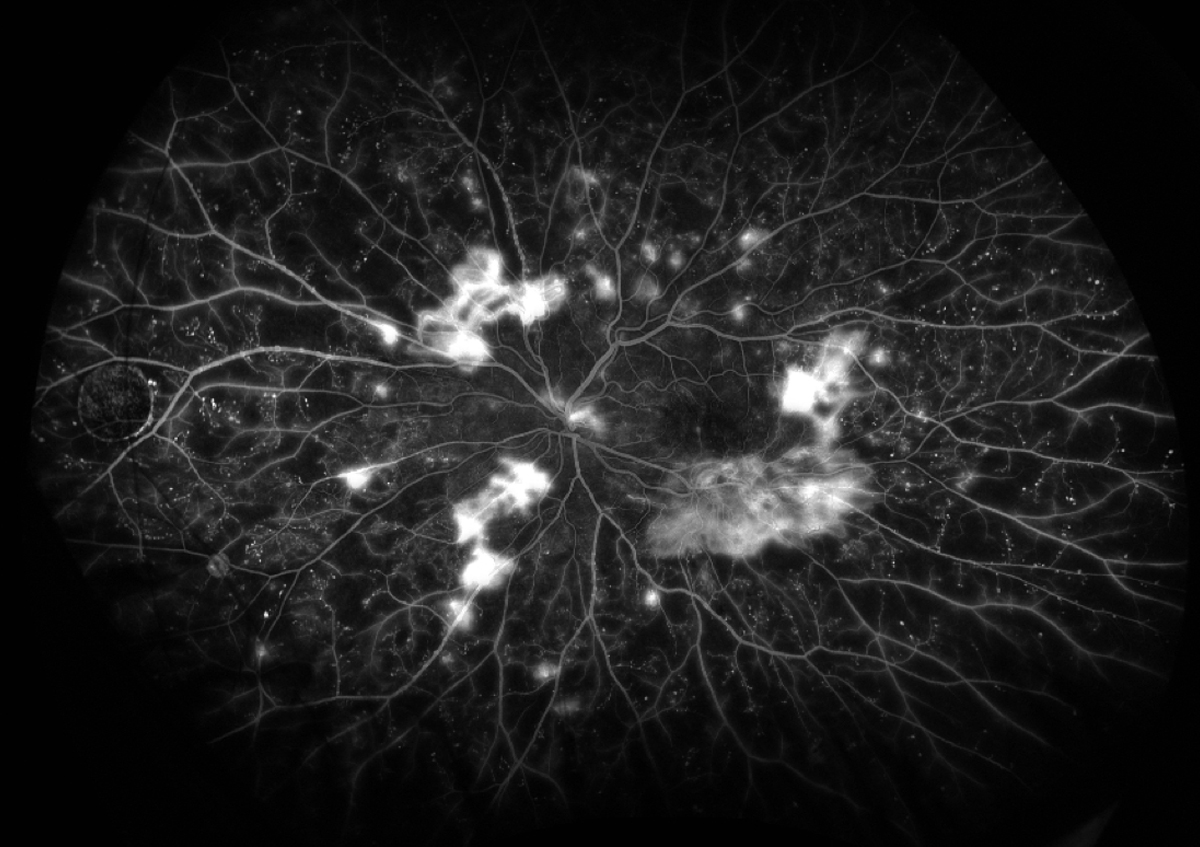

Ultrawide-field imaging continues to provide incredible images of the retina and retinal periphery, even in patients with small pupils. Combining ultrawide-field imaging with fluorescein angiography provides unparalleled evaluation from the macula to the periphery, allowing clinicians to evaluate neovascularization or peripheral capillary nonperfusion (Figure 2).

Figure 2. Proliferative diabetic retinopathy as seen on ultawide-field fluorescein angiography.